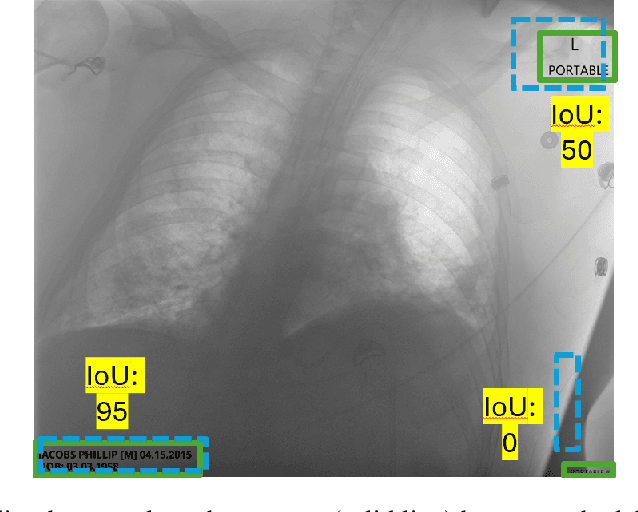

Abstract:Access to medical imaging and associated text data has the potential to drive major advances in healthcare research and patient outcomes. However, the presence of Protected Health Information (PHI) and Personally Identifiable Information (PII) in Digital Imaging and Communications in Medicine (DICOM) files presents a significant barrier to the ethical and secure sharing of imaging datasets. This paper presents a hybrid de-identification framework developed by Impact Business Information Solutions (IBIS) that combines rule-based and AI-driven techniques, and rigorous uncertainty quantification for comprehensive PHI/PII removal from both metadata and pixel data. Our approach begins with a two-tiered rule-based system targeting explicit and inferred metadata elements, further augmented by a large language model (LLM) fine-tuned for Named Entity Recognition (NER), and trained on a suite of synthetic datasets simulating realistic clinical PHI/PII. For pixel data, we employ an uncertainty-aware Faster R-CNN model to localize embedded text, extract candidate PHI via Optical Character Recognition (OCR), and apply the NER pipeline for final redaction. Crucially, uncertainty quantification provides confidence measures for AI-based detections to enhance automation reliability and enable informed human-in-the-loop verification to manage residual risks. This uncertainty-aware deidentification framework achieves robust performance across benchmark datasets and regulatory standards, including DICOM, HIPAA, and TCIA compliance metrics. By combining scalable automation, uncertainty quantification, and rigorous quality assurance, our solution addresses critical challenges in medical data de-identification and supports the secure, ethical, and trustworthy release of imaging data for research.